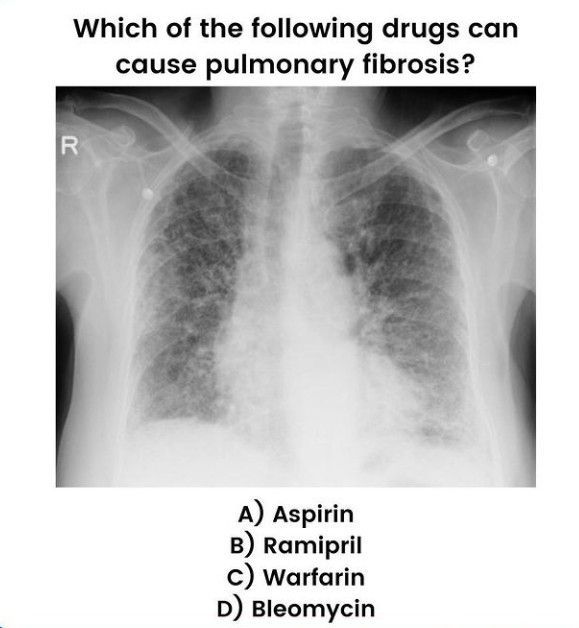

Identify the pulmonary fibrosis causing drug.